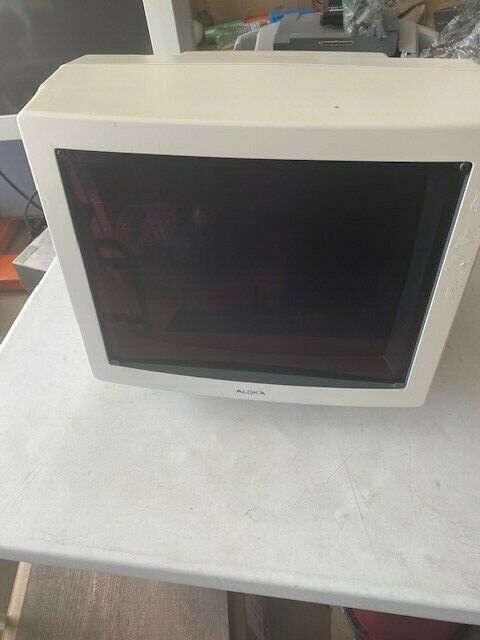

DIAGNOSTIC ULTRASOUND MACHINES FOR SALE

ALOKA 650 CL ULTRASOUND MACHINE WITH CONVEX PROBE

Sale price$ 2,786.60